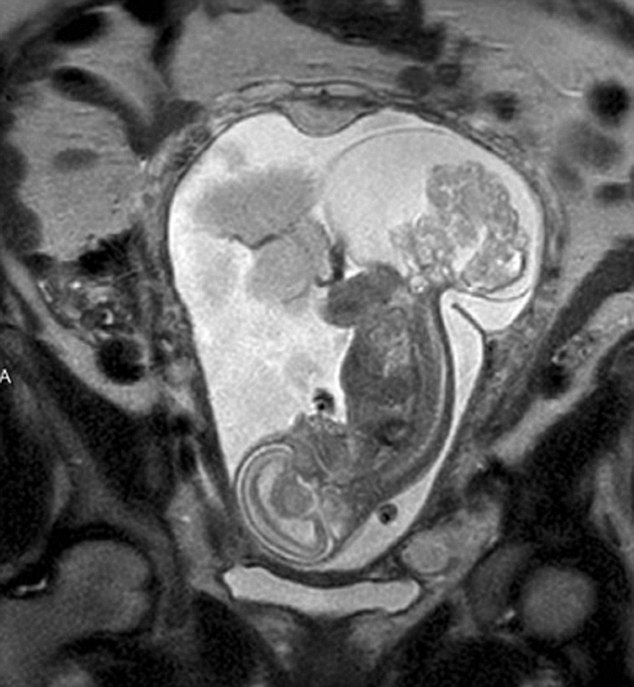

【環球網綜合報道】據英國《每日郵報》10月23日報道,美國得克薩斯州布蘭諾市的女子瑪格麗特·伯默(Margaret Boemer)懷孕16周時去做產檢,不幸被告知胎兒尾骨上長有腫瘤,她與醫生商量后決定先將胎兒取出進行腫瘤切除手術,再將其送回子宮繼續孕育。最終手術圓滿成功,12周后胎兒足月出生。

瑪格麗特稱自己當時聽到產檢結果時十分害怕。“醫生說寶寶長了骶尾部畸胎瘤。我們很震驚,很害怕,因為我們根本不知道這個什么瘤到底意味著什么。”隨著時間流逝,腫瘤越來越大,胎兒滿23周時腫瘤已危及其性命。醫生告訴瑪格麗特,若想胎兒存活,只能將胎兒取出進行手術,然后再放回子宮,否則只能立即終止孕期。“這很容易做決定:讓腫瘤奪去孩子性命,或是給孩子存活的機會。我們當然選擇后者。”瑪格麗特說。

醫生將胎兒取出20分鐘后,便放回母體子宮。12周后,寶寶足月出生。瑪格麗特稱:“這可以說是她的第二次出生了。只要她有機會活下來,我愿意承受所有風險。”(實習編譯:高睿 審稿:朱盈庫)